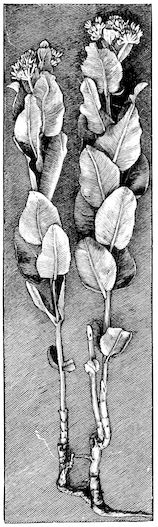

Fig. 6.—Osseous cachexia. This condition developed in two months, the last month of gestation and the first of lactation.